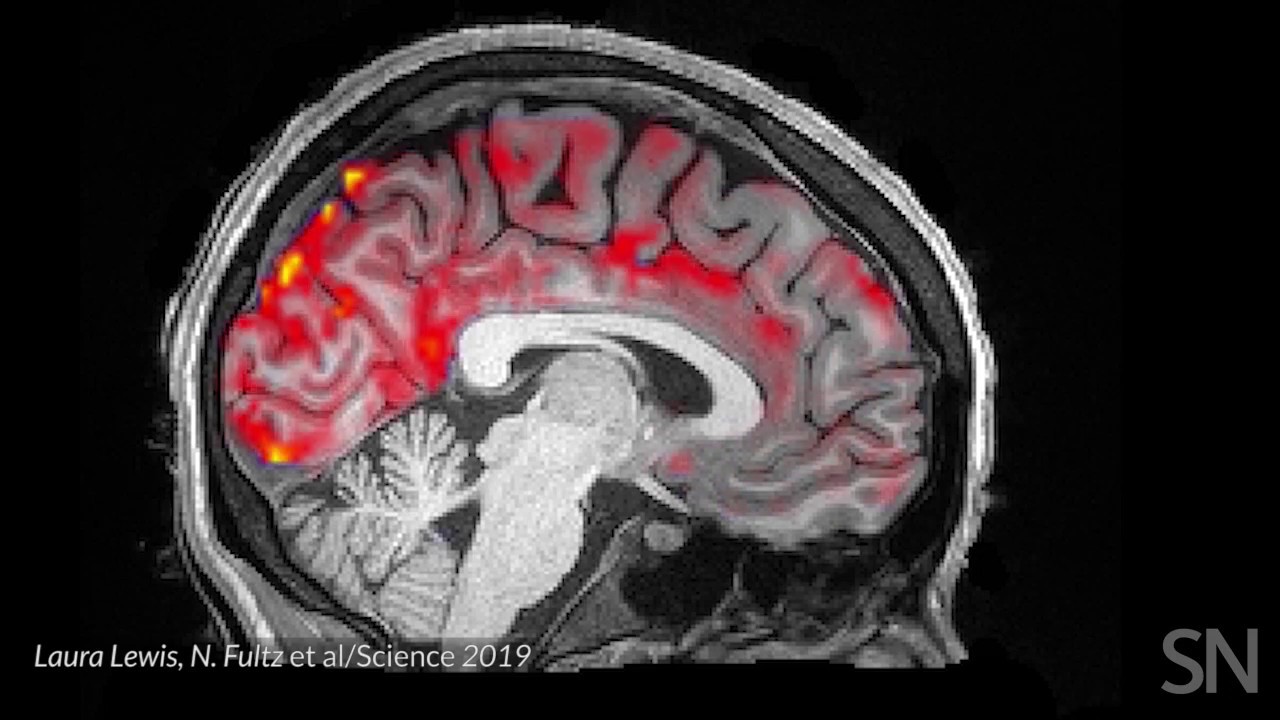

Впервые в истории современной медицины, ученым удалось понять, как спинномозговая жидкость циркулирует в головном мозге человека во время сна. При этом открытие ученых из Бостонского университета поможет не только лучше понять физиологию, но и узнать о том, как формируются некоторые неврологические и психические расстройства.

Исследование, опубликованное в журнале Science, иллюстрирует, что циркуляция спинномозговой жидкости во время сна тесно связана с мозговой активностью мозговых волн и кровотоком. Причем, что интересно, наиболее интенсивно эти процессы происходят во время сна.

После того, как человек засыпает, его нейроны «успокаиваются», — говорит доцент кафедры биомедицинской инженерии Бостонского университета Лаура Льюис. Вслед за этим кровь начинает покидать некоторые области мозга и освобождать место для спинномозговой жидкости, которая «промывает» головной мозг ритмичными импульсами, синхронизированными с активностью мозговых волн.

Совместная работа мозговых волн с кровотоком и спинномозговой жидкостью также может дать представление о различных возрастных нарушениях. Более ранние исследования показали, что поток ликвора и волновая активность мозга помогают «вымывать» токсичные продукты из мозговых тканей. В частности, ряд белков, в том числе и тех, что, накапливаясь, вызывают развитие болезни Альцгеймера.

Более того, поскольку люди стареют, их мозг начинает

генерировать меньше медленных волн. В свою очередь, это может повлиять

на кровоток в головном мозге и уменьшить циркуляцию спинномозговой

жидкости во время сна, что приводит к накоплению токсичных белков и

снижению памяти. Хотя исследователи, как правило, оценивают эти процессы

по отдельности, теперь кажется, что они очень тесно связаны.